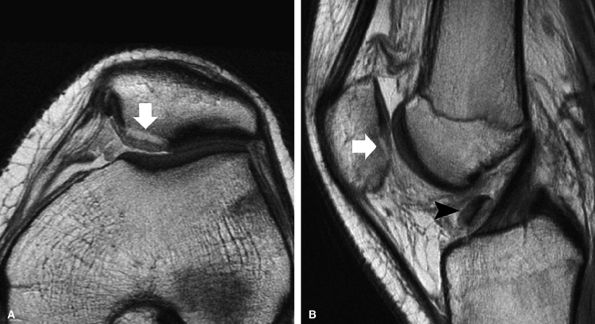

![]() |

FIGURE 7.18 ● Prospective MR evaluation of a bone bruise in the knee of a 28-year-old man with a complete ACL tear. Sagittal fat-suppressed (A) and fast spin-echo (B) MR images obtained at the time of injury demonstrate characteristic bone marrow edema with compression of cartilage over the lateral femoral condyle (white arrow). A sagittal MR image obtained 19 months later (C) demonstrates proud subchondral bone with focal cartilage loss over the condyle (black arrow), as well as flap formation over the tibial plateau (arrowhead). (Reprinted by permission of SAGE Publications, Inc., from Am J Sports Med, in press.)